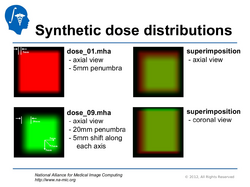

SlicerRT

Qualitative and quantitative comparison of two RT dose distributions

Dose accumulation for adaptive radiation therapy

- Tutorial presentation: pptx pdf

- Dataset: download from MIDAS

- Authors: Csaba Pinter, Andras Lasso, Queen's